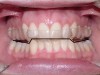

The position, shape, length, and inclination of the maxillary canines will affect the anterior frenal midline position of the mandible. This position may or may not coincide with the midline of the teeth, but gives an indication of the location of the left and right condyles in their fossae. The canines serve as lateral positioners of the mandible. The more lingual the maxillary canine inclination on one side, the more the mandible will shift to the opposite side and the condyle distalize on the opposite side (Figure 6, Figure 7 and Figure 8).

Figure 6  The inclination of the canines provide  the midline position of the mandible. When these  teeth are inclined (eg, the right canine in this  case), they tend to shift the mandible away from  the midline (in this case toward the left).

Figure 6

Figure 7  The left side of the patient shows how  maxillary molars and premolars can cause the  mandibular molars to be lingually inclined as  the teeth come into occlusion.

Figure 7

Figure 8  This case shows the shift of the  mandible from the point of first contact to full  closure because of the anterior restriction, which  has caused the mandible to shift posteriorly and  to the left. This patient experienced symptoms  of right lateral pterygoid tenderness with left  TMJ pain, left-sided headaches, and neck stiffness.  Release of this restriction allowed the  mandible to reposition itself to the midline with  reduction of the symptoms.

Figure 8